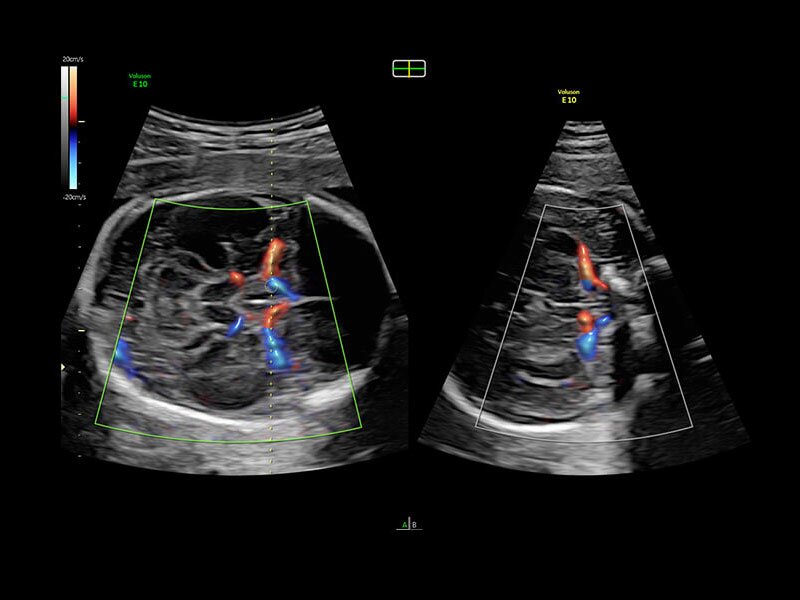

• Высокочувствительный допплер (HD-Flow)

• Реалистичный объёмный кровоток в режиме ЦДК (Radiantflow)

• HDlive Flow - перемещаемый источник света, совместимый с визуализацией кровотока в 3D

• HDlive Flow Silhouette - режим "Силуэт" с выделением границ полостей сердца и сосудов, совместимый с визуализацией кровотока

• Advanced STIC - расширенный программный пакет для исследования сердца плода в режиме 4D для механических и электронных объемных датчиков:

• Использование цветного, энергетического допплера, В Flow - режим STIC.

• Сочетание с М-режимом - STIC-M-Mode

• Перемещаемый источник света - STICflow

• SonoVCADHeart - программное обеспечение для исследования сердца плода в режиме 3D/4D (быстрый доступ к плоскостям сканирования) по рекомендациям ISUOG

• Технология HDlive Flow — повышает реалистичность визуализации сосудистых структур, улучшая восприятие глубины (по сравнению с традиционным цветовым допплером и функцией HD-Flow).